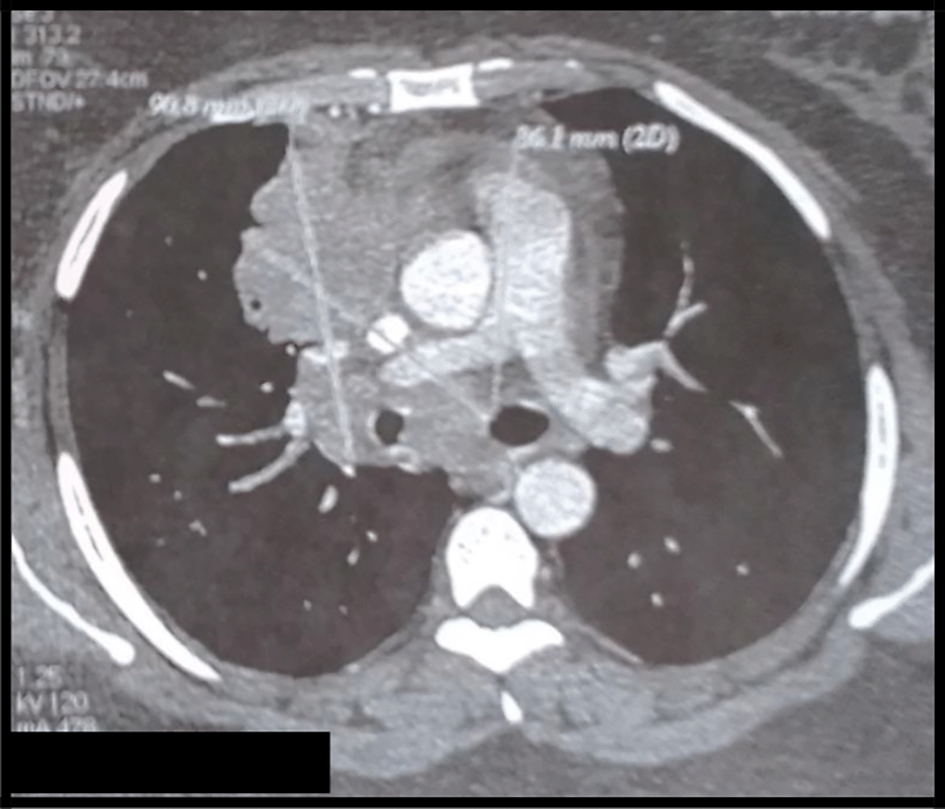

The body computed tomography (CT) scans revealed a bulky mediastino-hilar tumor in the right chest, measuring (90 x 85 x 71 mm), invading the right main bronchus, extending to the vena cava and infiltrating the pericardium with a subpleural right node (Figures 2 and 3). Bronchoscopy showed a polypoid mass located in the carina, involving the right main bronchus. Cytology revealed malignant cells. Histopathology of the bronchial biopsy did not show any malignant lesions. In addition, we performed a biopsy of the supra-clavicular adenopathy. Histopathology revealed an intense staining for CD15 and CD30 with large multinuclear reed Sternberg cells. Therefore, the diagnosis of an Hodgkin lymphoma was confirmed.